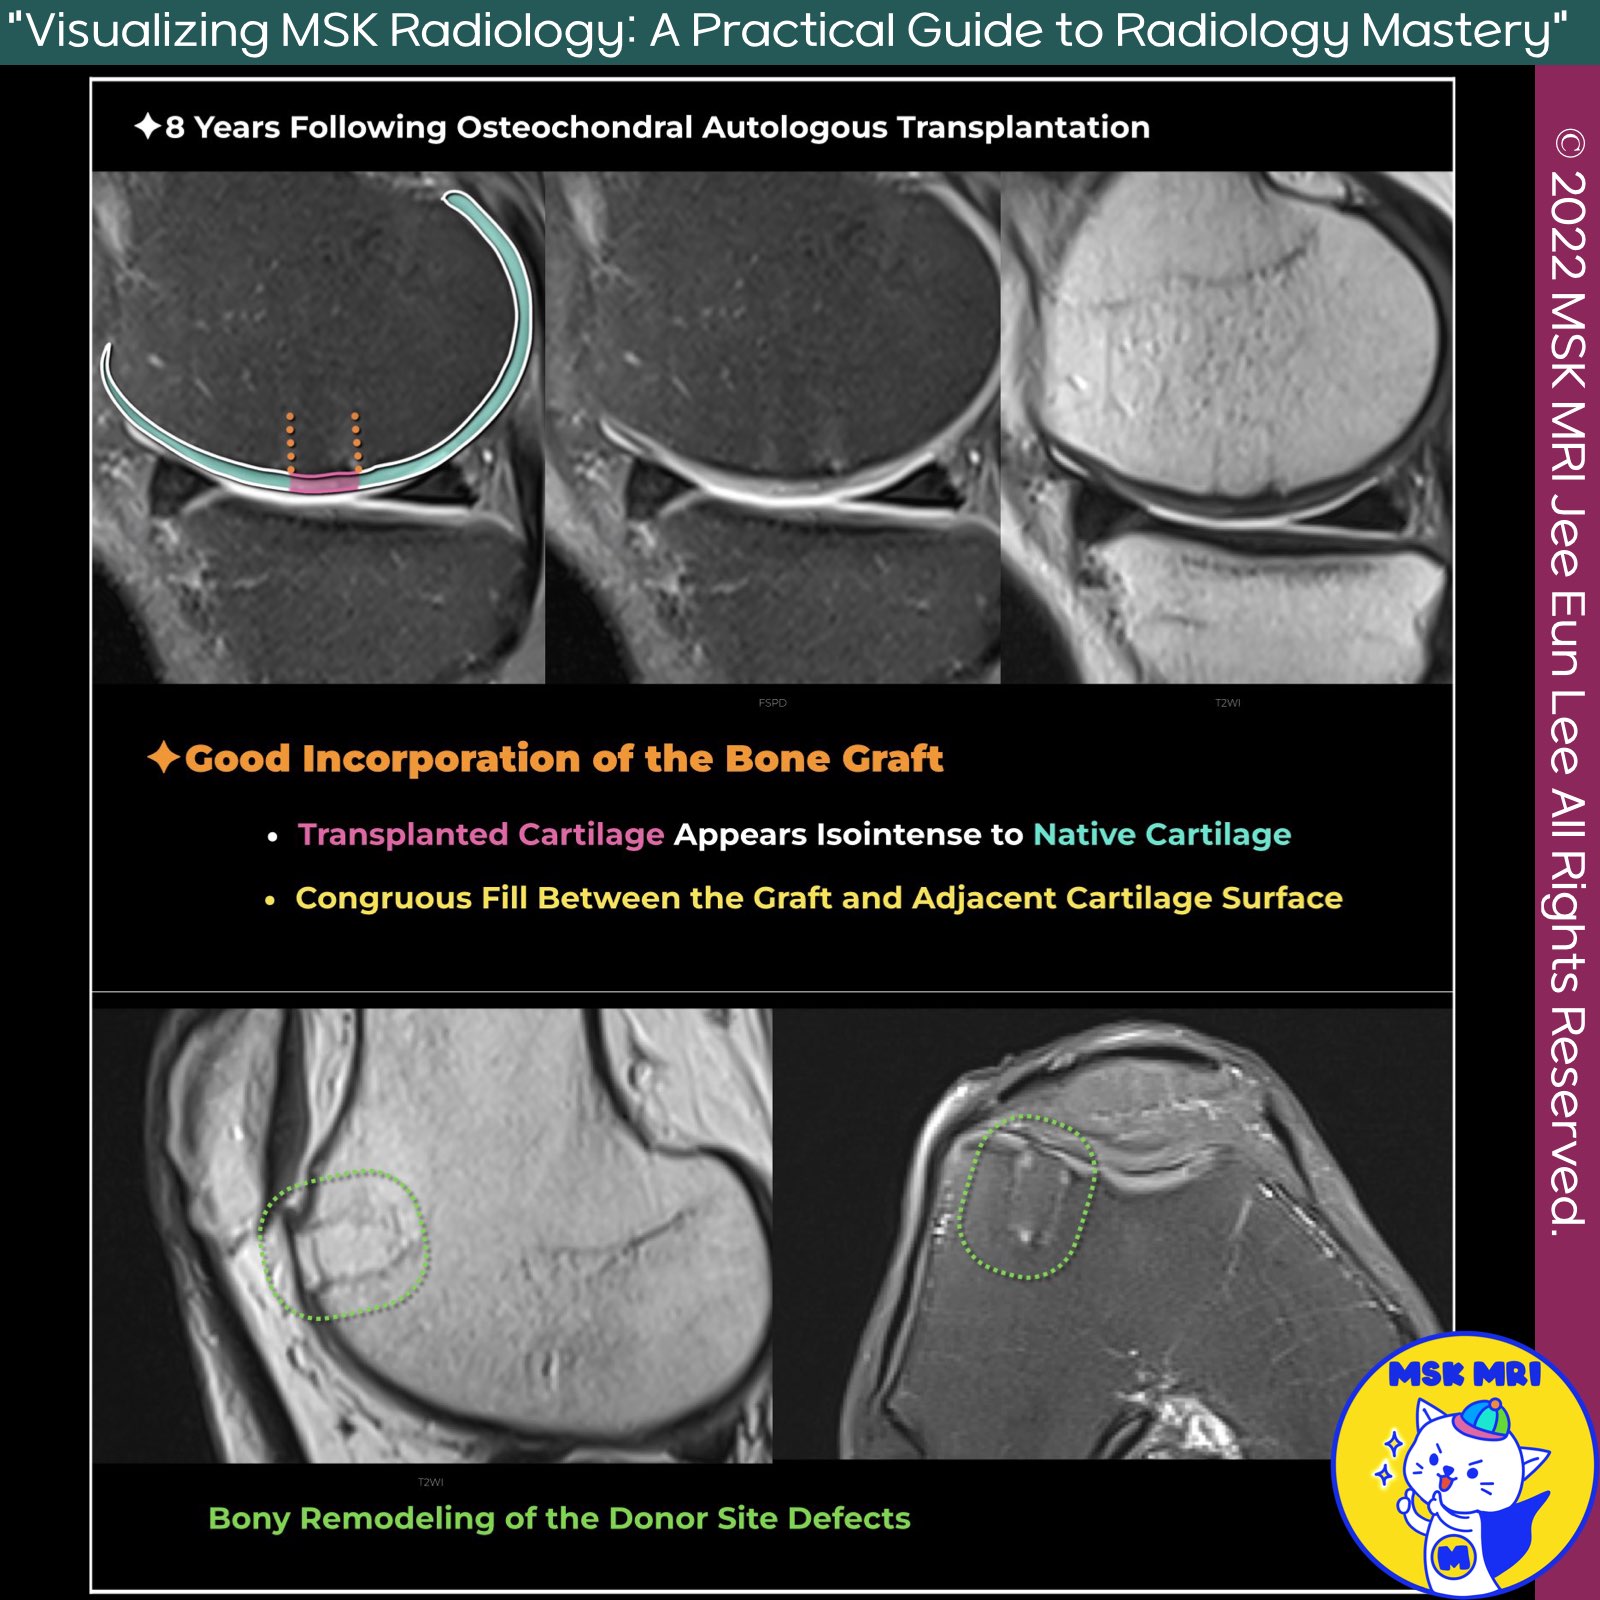

📌 Osteochondral Autograft Transplantation (OATS)

- Osteochondral Autograft Transplantation (OATS), or Mosaicplasty, is a surgical technique used to treat focal cartilage lesions in the knee by transplanting osteochondral cylinders from non-weight-bearing areas to damaged cartilage areas.

✅ Postoperative Imaging and Outcomes

- Assessment: Evaluate morphology of native and donor cartilage, fill defects, peripheral integration, and joint surface restoration.

- Early Healing: Transplanted tissue should fill the defect uniformly without gaps.

- Cartilage Thickness: Ideal match to surrounding cartilage, though patellar defects may present challenges.

✅ Healing and Complications

- Bone Marrow Edema: Common early postoperatively, typically resolves by 6 months.

- Donor Site Healing: Fills with fibrocartilage in 6-9 months; persistent edema may indicate morbidity.

- Edema Regression: Similar regression rates in donor and repair sites.